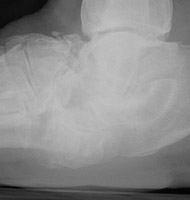

Charcot Joint: AP -Charcot Joint: Lateral - Disorganization of Chopart jointNEUROPATHIC JOINT DISEASE (CHARCOT JOINT) articular degeneration secondary to weight-bearing trauma and neurovascular changes on sensory deficient joint, resulting in bony resorption and formation.

Osteophytes, joint effusions, and soft tissue swelling are among the common early findings. Later in the disease process, acute fractures, dislocations, and subluxations may occur. Subluxations at the tarso metatarsal joints may mimic Lisfranc fracture/subluxations. Frequent fractures include subchondral fractures of the second metatarsal head, and avulsion fractures of the posterior calcaneal tubercle. Tapering osteolysis ("sucked candy" or "pencil-pointing"), bony fragmentation with well defined margins, and fusions with or without pseudoarthroses are other signs of progression.